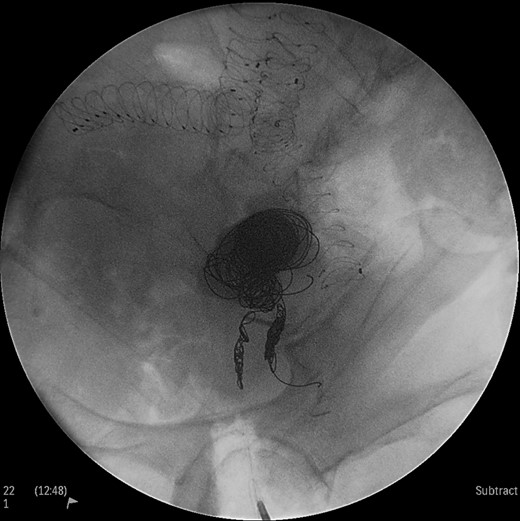

Under general anesthesia the patient was placed in prone position and a 15 cm transverse incision, slightly curvy was performed in the middle part of the right gluteal region between the posterior superior iliac spine and ischiac tuberosity. The gluteus maximus muscle was split and the inferior gluteal artery was identified as it entered the gluteal region through the greater schiatic foramen near the schiatic nerve below the piriformis muscle. The inferior gluteal artery was punctured using Seldinger technique and a 4Fr was introduced into the artery (Fig. 2). An angiography was made revealing the aneurysm of the right IIA and two feeding arteries, inferior gluteal artery and probably a branch of superior gluteal artery, filling the sac (Fig. 3). A 0.014 inch Pilot guide wire (Boston Scientific Corporation, USA) was inserted into the aneurysm and a microcatheter 3 Fr RENEGADE STC (Boston Scientific Corporation, USA) was advanced over the wire. After removing the wire, embolization microcoils (Interlock, Boston Scientific, USA) (two coils 22–600 mm, two coils 20–500 mm, three coils 18–500 mm) were introduced into the aneurysm sac (Fig. 4). A 5 Fr sheath was subsequently placed, a 5Fr RIM catheter (Cordis, USA) was advanced to the aneurysm sac through a 0.035 inch Terumo guide wire (Glidewire, Terumo Corporation, Japan) and selective catheterization of the second feeding artery was performed (Fig. 5). Embolization coils (Interlock, Boston Scientific, USA) were inserted into the two feeding arteries (two coils 15–400 mm) (Fig. 6). Completion angiogram depicted absence of blood flow into the aneurysm and the runoff vessels (Fig. 7). The patient had an uneventful recovery period without buttock claudication, ischemic complications and discharged in good condition. A follow-up CT aortography after 6 months depicted complete thrombosis of the aneurysm (Fig. 8).

Intraoperative angiogram showing the presence of the aneurysm and two collateral vessels, embolization with coils of the sac and two feeding arteries. Completion angiogram depicted absence of blood flow in the IIA aneurysm and the runoff arteries.